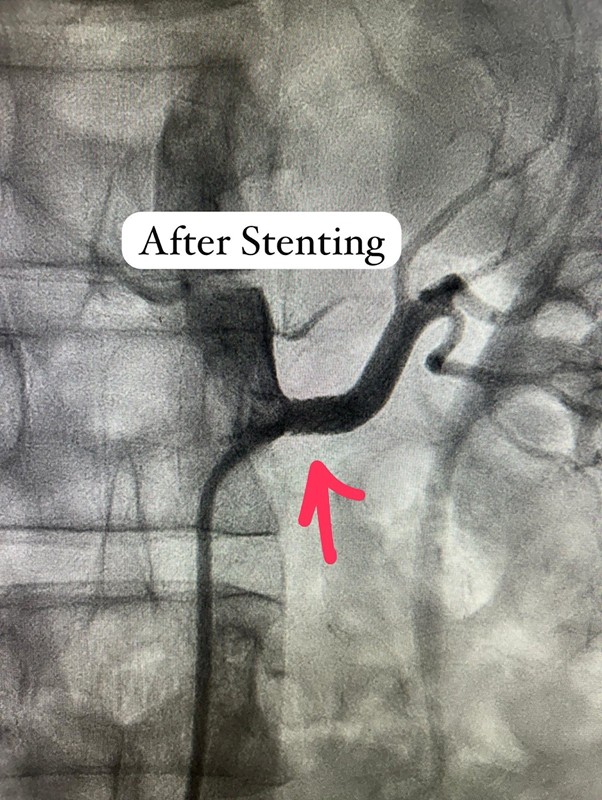

After a few weeks of medical therapy, a repeat CT Angiography showed partial recanalization of the previously occluded subclavian artery, indicating a positive response to treatment. To further define the anatomy and plan intervention precisely, Digital Subtraction Angiography (DSA) was performed. Based on these findings, Dr. Ingle successfully carried out a subclavian artery angioplasty, restoring critical blood flow to the affected limb and reducing future neurological risk.

This case highlights the critical role of thorough clinical judgment, advanced imaging techniques such as DSA, and timely, minimally invasive intervention in managing complex vascular diseases. Most importantly, it reflects a commitment to treating not just isolated lesions, but the patient as a whole—leading to safer decisions, better outcomes, and renewed hope.